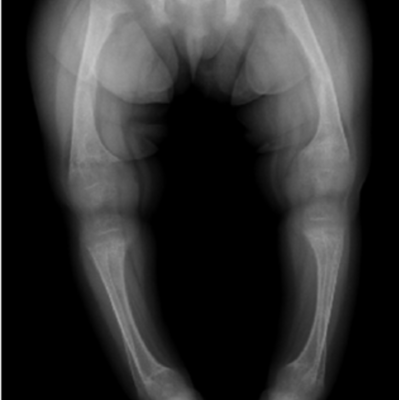

Children with rickets show various bone deformities like flaring of wrists and ankles, frontal bossing or prominence of front skull bones, bowlegs and bead-like swellings on ribs. Severe rickets can lead to easy fractures and even stunted growth.